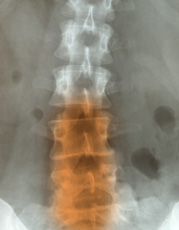

Akute und chronische Wirbelsäulen – Gelenk – und Muskelerkrankungen

Viele Betroffene denken, dass gerade bei Rückenproblemen und Bandscheibenschäden Therapien mit zahllosen Injektionen, oder eine Operation das Mittel der Wahl wäre. Dem gegenüber steht die Osteopathie und Chiropraktik, die Behandlung mit der Hand und andere alternative Therapien.